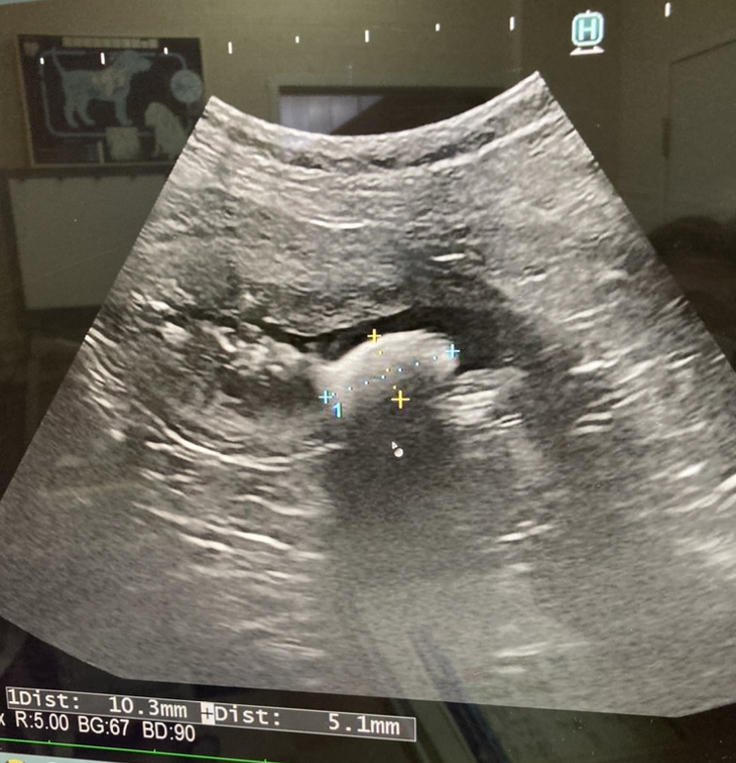

最近の心臓画像です。

以前より心臓が肥大しているとの事でした。